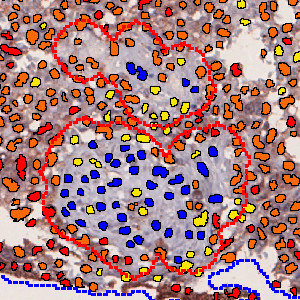

Nuclei surrounded by CD74 negative, low and intermediate staining.

The “10130 – CD74, Melanoma, TME” APP detects nuclei and classifies them as either negative, 1+, 2+ or 3+ based on the CD74 staining expression present in each nucleus’ vicinity.

To identify the nuclei, the APP performs a two-stage polynomial blob filtering on a blue-enhanced feature image and delimits them using local linear filtering. Each pixel with DAB staining is classified as low, mid and high based on the intensity and grouped together locally. Each nucleus is then classified based on its surroundings in the order of 3+, 2+, 1+ and negative to emphasize the strongest staining present in each nucleus’ vicinity.